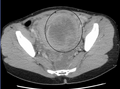

A very large (9 cm) fibroid of the uterus which is causing pelvic congestion syndrome as seen on CT